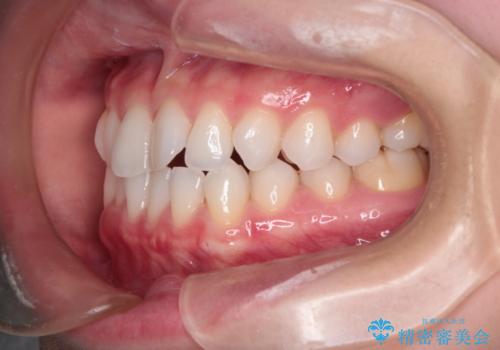

【インビザライン】前歯の凸凹をマウスピース矯正でなおしたい

- 前歯の凸凹を主訴に来院されました。

上の前歯は翼状捻転と呼ばれる状態でしたが、奥歯の遠心移動を行うことで配列スペースを確保することで綺麗に歯を並べることができました、

途中でインビザラインの使用時間が短くなってしまったため期間が予定より少し伸びましたが、1年半で満足いく結果となり患者様に喜んでいただけました。

下顎骨が右側に偏位していることにより下顎前歯の真ん中はずれています。